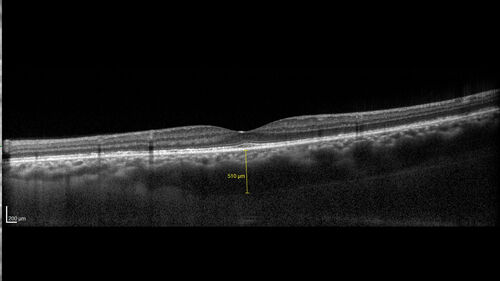

43 year old man: initial presentation - The vision in the left eye is blurry and opaque for about 2 weeks.  In the central of the vision, when he covers the right eye, in the center of the left eye there is a film with a light in the middle.  This has never happened before.  He has not been sick for the last few months.  A few weeks ago he saw waves on the floor when looking down but that has gone away.  Since the vision loss started the vision has not changed much.  The central vision is not getting better.

VA improved over 2 months to normal.  Then the patient had 2 more episodes of self-limited vision loss (no treatment).  Then 2 years later he presented with a diagnosis of CNS lymphoma and later developed subretinal deposits (last images)